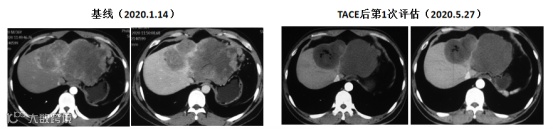

对于伴有中大量腹水的肝癌患者,TACE治疗的决策需基于腹水成因的鉴别诊断。其中,门脉高压性腹水患者通常被视为TACE禁忌证;而对于癌性腹水患者,若肝功能代偿良好,经多学科评估后可谨慎实施TACE。作者在临床实践中发现,此类患者接受TACE和系统治疗后,不仅不会加重腹水和肝功能损害,反而可能通过控制肿瘤进展而改善腹水(图1)。

图1. 癌性腹水患者经TACE联合靶向治疗后腹水消退